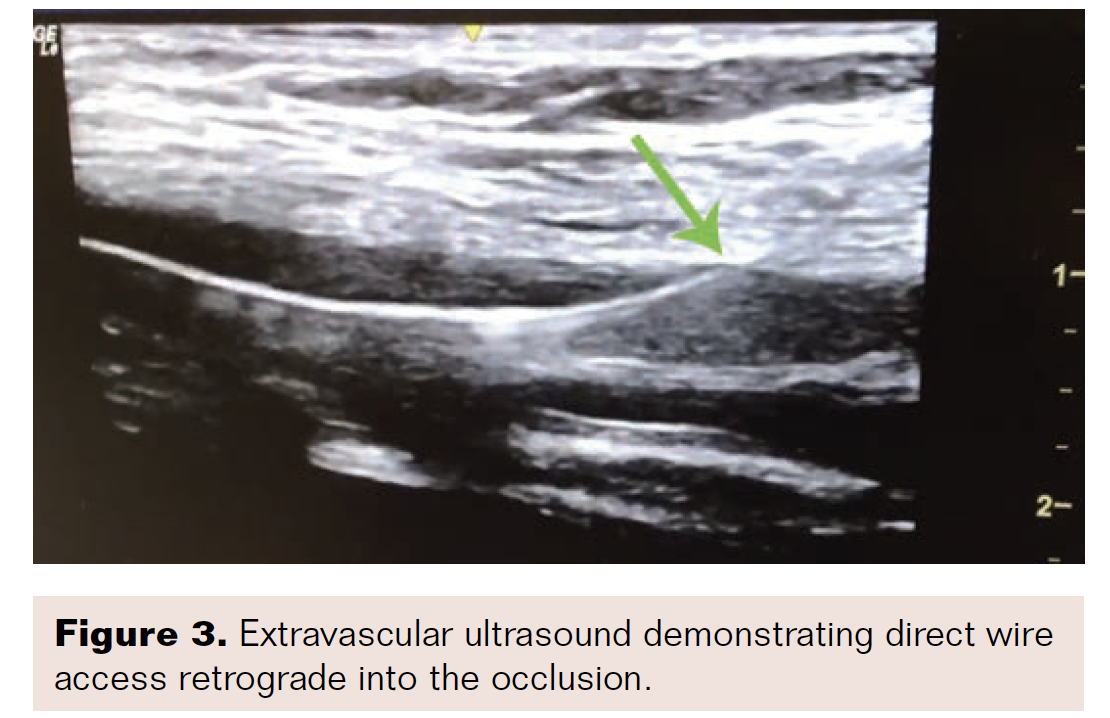

A 5 French (Fr) 11 cm sheath that was initially placed in the right CFA was exchanged over a wire for a 7 × 45 cm sheath that was advanced “up and over” and placed antegrade at the ipsilateral left CFA. Brief unsuccessful attempts were made with .018-inch and .014-inch wires to cross the SFA given the calcific proximal “flush” occlusion, with wires favoring the open profunda artery (Figure 2A). Using extravascular ultrasound visualization, a micropuncture needle tip (Cook Medical) was advanced retrograde directly into the proximal left SFA 100% occlusion, and a .014-inch wire was advanced through a needle into the occlusion and across the proximal cap into the left

CFA (Figures 3, 4, and 5A).

Pedal access techniques have improved the success of intervening in these types of SFA occlusions, as these caps can be approached retrogradely.5 Despite this improvement, the pedal approach does not guarantee that a retrograde wire can be maintained intraluminally, or even if luminal, that the CFA can be reentered. Approaching the proximal SFA occlusion directly under extravascular ultrasound guidance retrograde with a micropuncture needle (Figures 3, 4, and 5A) allows for the visualization of the needle tip well enough to ensure that the wire is intraluminal and also provides great support to advance both 0.014-inch and 0.018-inch wires, both hydrophilic tip and heavy gram wires, with excellent control. The wire can then be advanced into the previously placed antegrade sheath, and a microcatheter can be advanced antegrade past the proximal cap and worked via the standard access (Figures 5B-C).